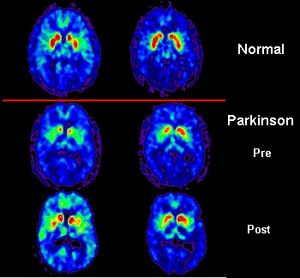

مرض پاركنسن (Parkinson's Disease) ، يُصنّف كخلل ضمن مجموعة اضطرابات النظام الحركي، التي تنتج بسسب خسارة خلايا الدماغ المنتجة للدوبامين إلا أنه أثبت وجوده في عائلات بعينها دون الأخرى .

في الحالة الطبيعية يكون هناك توازن بين الأستيل كولين والدوبامين.

في حال الإصابة بداء باركنسن يحدث نقص في إفراز الناقل العصبي الدوبامين، وبالتالي اختلال التوازن بين الدوبامين والأستيل كولين (الذي يزداد تركيزه على مستوى الـ CNS).